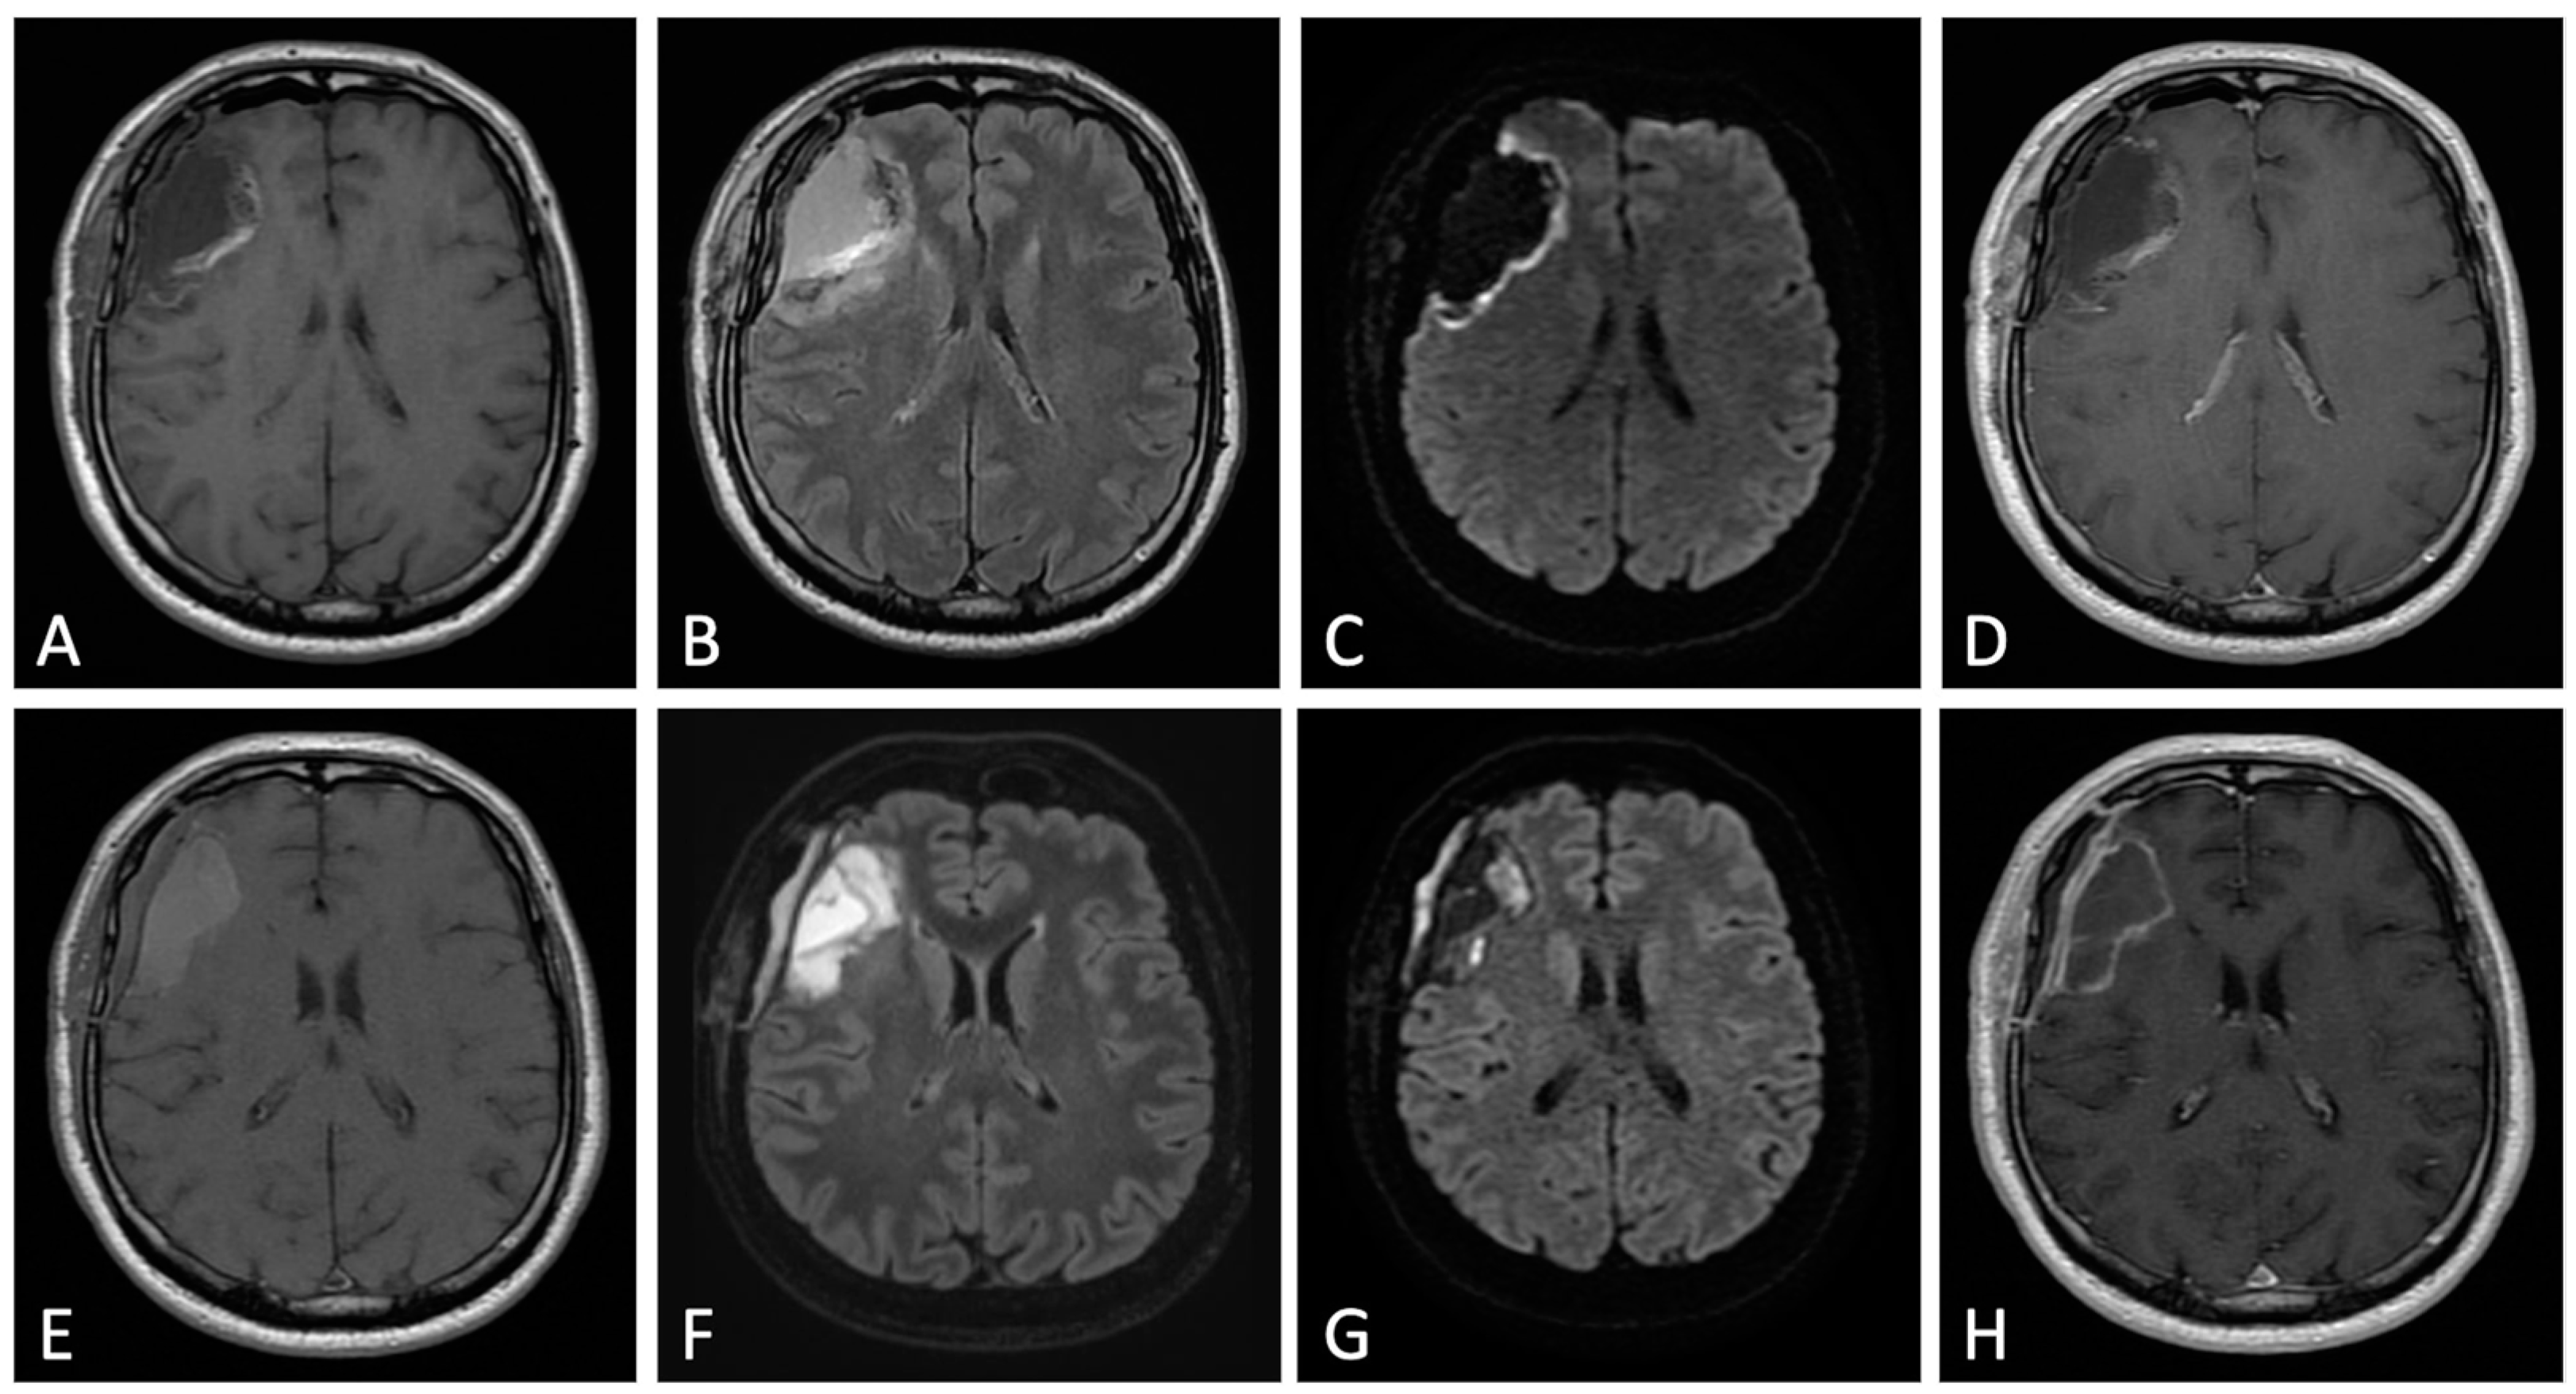

2. Early Post-Operative Imaging in Glioblastoma

3.3.2. Imaging: Conventional and Advanced MRI Sequences:

3.4.2. Imaging: Conventional and Advanced MRI Sequences